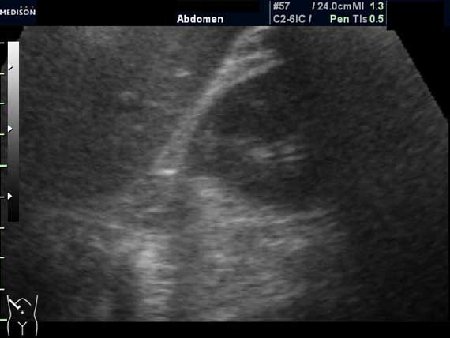

PS. Кстати, а что это у нее рядом с правым надпочечником?

Область правого надпочечника

PS. А надпочечник в срез не попал. Что-то, возможно, прилежит к области проекции надпочечника и к верхнему полюсу почки.